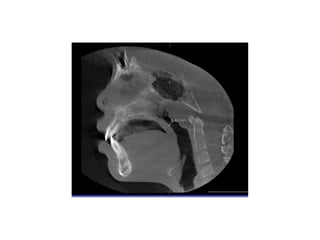

Obstruction of upper airways

Contributing factors

• Contributing factors in the obstruction of

upper airways include: anatomical airway

constriction, developmental anomalies,

macroglossia, enlarged tonsils and adenoids,

nasal polyps and allergic rhinitis.

• Enlarged adenoids as the major contributing

factor.